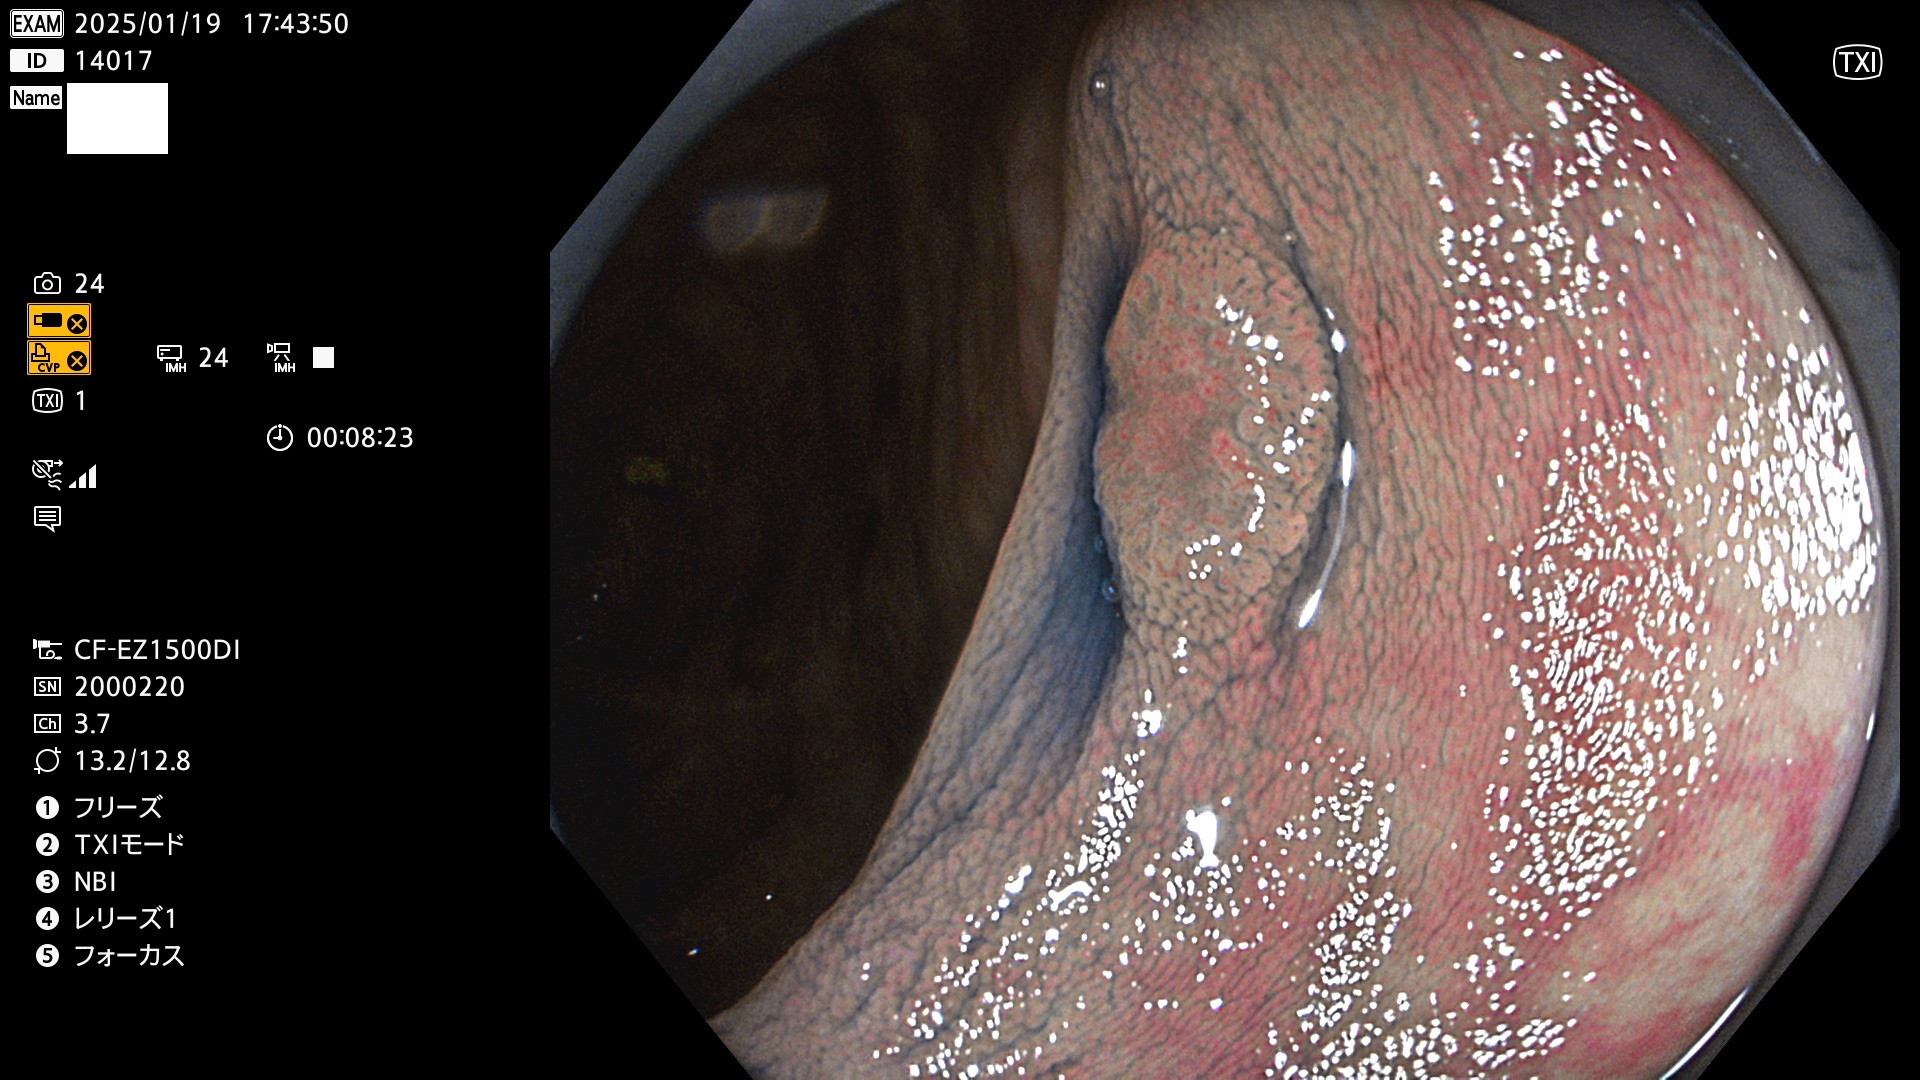

完全に平坦な物をUb、陥凹している物をUcと呼びます。最も発見が難しく危険な病変です。

毎週の検査(木・金・土・日)に発見されたUb、Uc型・腺腫を、その週の日曜の夜にUPし1週間、提示します。

抽出の対象期間 2025年1月16日〜1月19日の4日間(45件の検査)8個 (8/45=17%)